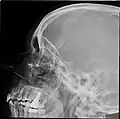

![]() Lateral projection of the paranasal sinuses | |

Paranasal sinuses radiograph (lateral)